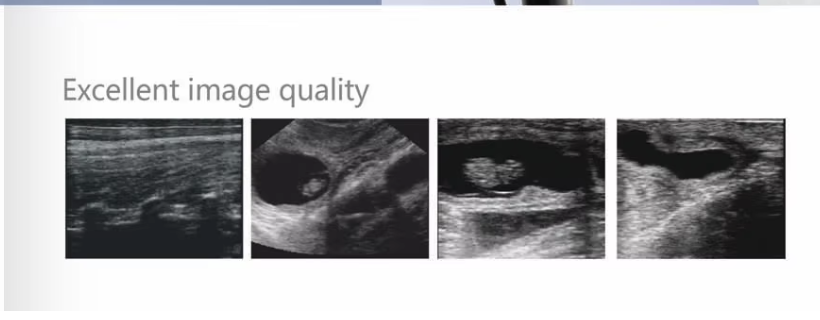

- Modo de visualización: B, B+B, B+M, M, 4B

- Tono gris: 256 niveles

- Procesamiento de imagen: color codificado, GAMA, histografía y suavización de imagen,